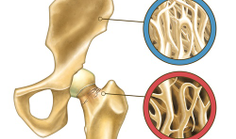

_ OsteoporosisSurgery to Repair Hip Fracture Saves Billions of $ By Sondra Forsyth articleEach year, more than 300,000 Americans -- primarily adults over age 65 -- sustain a hip fracture, a debilitating injury that can diminish life quality and expectancy and result in lost work days and substantial, long-term financial costs to patients, families, insurers and government agencies. Surgery, which is the primary treatment for hip fractures, successfully reduces mortality risk and improves physical function. However, little has been known about the procedure's value and return on investment.

_ OsteoporosisOxidative Stress Predicts Hip Fracture By Sondra Forsyth articleOxidative stress -- a disruption in the balance between the production of free radicals and antioxidants -- is a significant predictor for hip fracture in postmenopausal women, according to research led by University of Cincinnati epidemiologists and published online ahead of print in August 2014 in the Journal of Bone and Mineral Research.